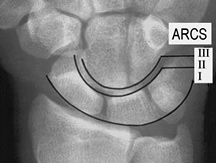

Figure 4: The carpal arcs

The carpal joint spaces should be symmetrical. The cortical margins of the bones should be parallel. One excellent way of looking at the positioning of the carpals is by using three carpal arcs. (Figure 4) The first arc is a smooth curve outlining the proximal convexity of the scaphoid, lunate and triquetrum. The second arc traces the distal concave surfaces of the same bones, and the third arc follows the main proximal curvatures of the capitate and the hamate.

An arc is disrupted if it cannot be traced smoothly. A break in one of the arcs indicates a fracture or the disruption of a ligament leading to a subluxation or dislocation.